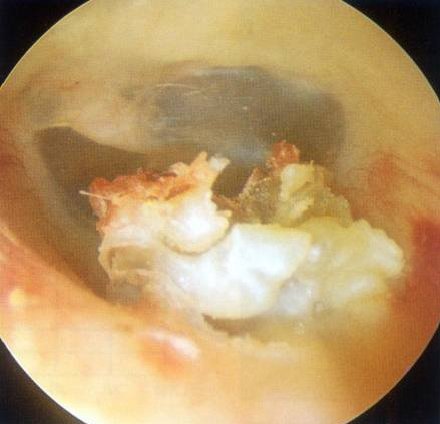

检查时可以见到外耳道内有灰白色或者黄色角蛋白碎屑、上皮样物堵塞,表面被多层鳞片状物包裹,外耳道皮肤充血、肿胀、糜烂,可伴有肉芽形成。较大的胆脂瘤清除后可以见到外耳道的骨质暴露,被破坏、吸收,外耳道骨段明显扩大,软骨段一般无明显改变。鼓膜一般是完整的,或充血,内陷,如果被胆脂瘤破坏,则会导致穿孔、萎缩和粘连。